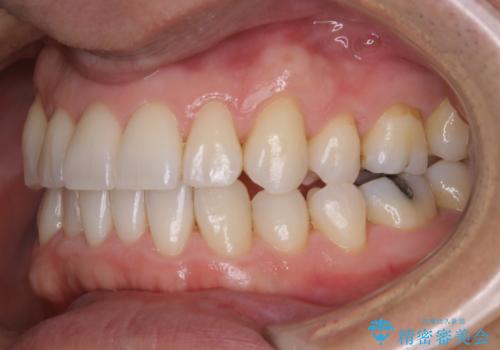

紅茶のステインをきれいにしたい

- 毎日紅茶を飲むため、歯のステインが気になるためキレイにしたいとのことでした。

PMTC60分コースを行いました。